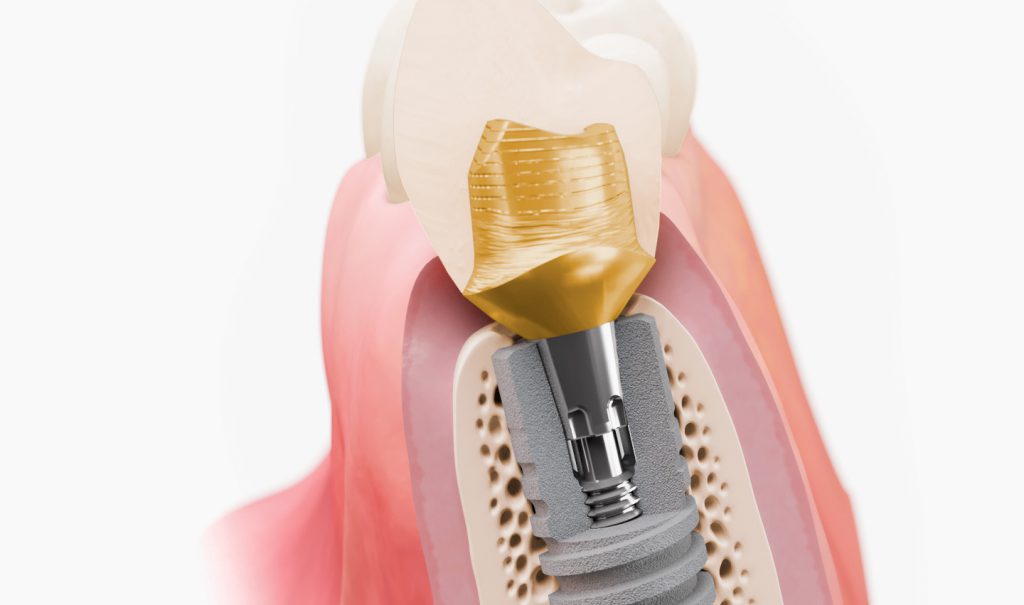

جراحی ایمپلنت دندان جراحی ایمپلنت دندان با قرار دادن ریشه دندان مصنوعی انجام می شود. این ایمپلنت ها با استخوان فک شما پیوند می خورند و به دندانپزشک یا جراح دهان و دندان اجازه می دهند